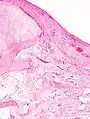

Histopathology of osteoarthrosis of a knee joint in an elderly female